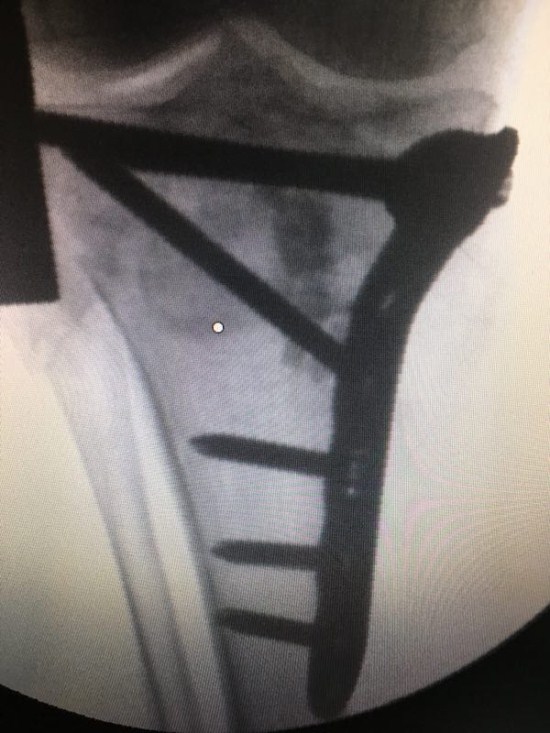

近日,显微骨科成功采用微创手术治疗一位高龄“ 熊猫血”患者。患者,女,84岁,蛛网膜下腔出血,左足、踝、腓骨多发骨折,BRh(-)血,为高龄稀有血型患者。入院后积极治疗及完善术前准备。于2017121日行“左胫骨平台骨折微创有限切开复位钢板螺钉内固定+植骨术”,手术切口小,出血量控制在20ml以内。术后在显微骨科全体医护人员的精心照顾下患者恢复良好,家属表示感谢。